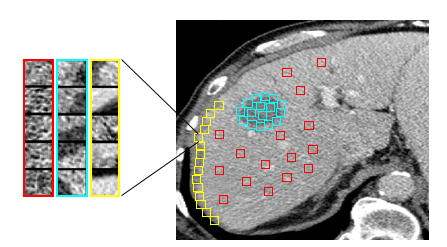

Refer to caption

(a)

(b)

Figure 1: (a) Liver patch examples: lesion (blue), normal-interior (red) and normal- boundary (yellow); (b) Patch size 20×20202020\times 20 [I] and patch size 50×50505050\times 50 [II]. Top row: lesion boundary patch examples; Bottom row: liver boundary patch examples.

2 Multi-class patch-based CNN system

We propose a system for lesion detection, which is based on localized patch classification into lesion vs non-lesion categories. Patches are an important representation to address the data limitation challenge, critical for modeling small and rare events such as lesions. Fig. 1a shows examples of lesion patches, including lesion-boundary patches (shown blue zoomed-in), as well as patches from the non-lesion category, which include both normal-interior patches (red) and normal-boundary patches (yellow). As can be seen in Fig. 1b[I], liver boundary and lesion boundary areas may look alike and are difficult to distinguish when using small patches. When using a larger size window, a clearer distinction between the two categories is possible, as seen in Fig. 1b[II]. This motivated us to use two different scales (patch-sizes) within the proposed system to capture both the local fine details and the more global spatial information.

Patches are extracted from 2D liver CT scans with an expert marking for the lesions. The liver area can be segmented automatically or by an expert. The patches are labeled with their corresponding class k𝑘k \in {lesion, normal-interior, normal-boundary}, automatically, according to their relative position to the boundary. The patches are extracted around each pixel in two fields-of-view (FOV) of size 20×20202020\times 20 pixels and 50×50505050\times 50 pixels. The patches contain localized information as well as spatial context. All patches are resized to 32×32323232\times 32 pixels to fit the input image size of our multi-class CNN architecture.